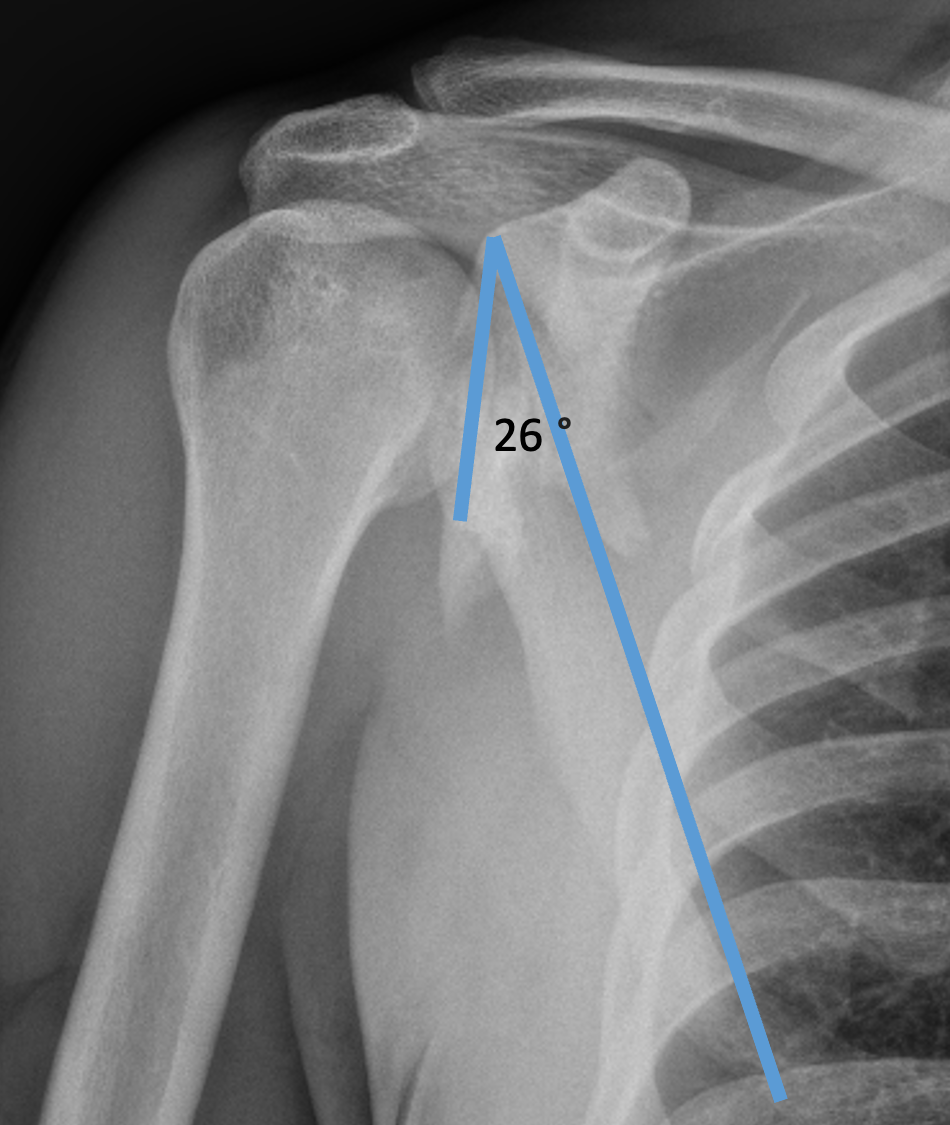

| Glenoid neck displacement | Glenoid neck angulation | Glenopolar angle |

|---|---|---|

| > 2cm medial displacement | > 45° angular deformity | < 22° glenopolar angle |

Glenopolar angle

Definition

- line connecting the superior and inferior glenoid fossa

- line connecting the superior pole of glenoid and inferior angle scapula

- normal 30 - 40 degrees